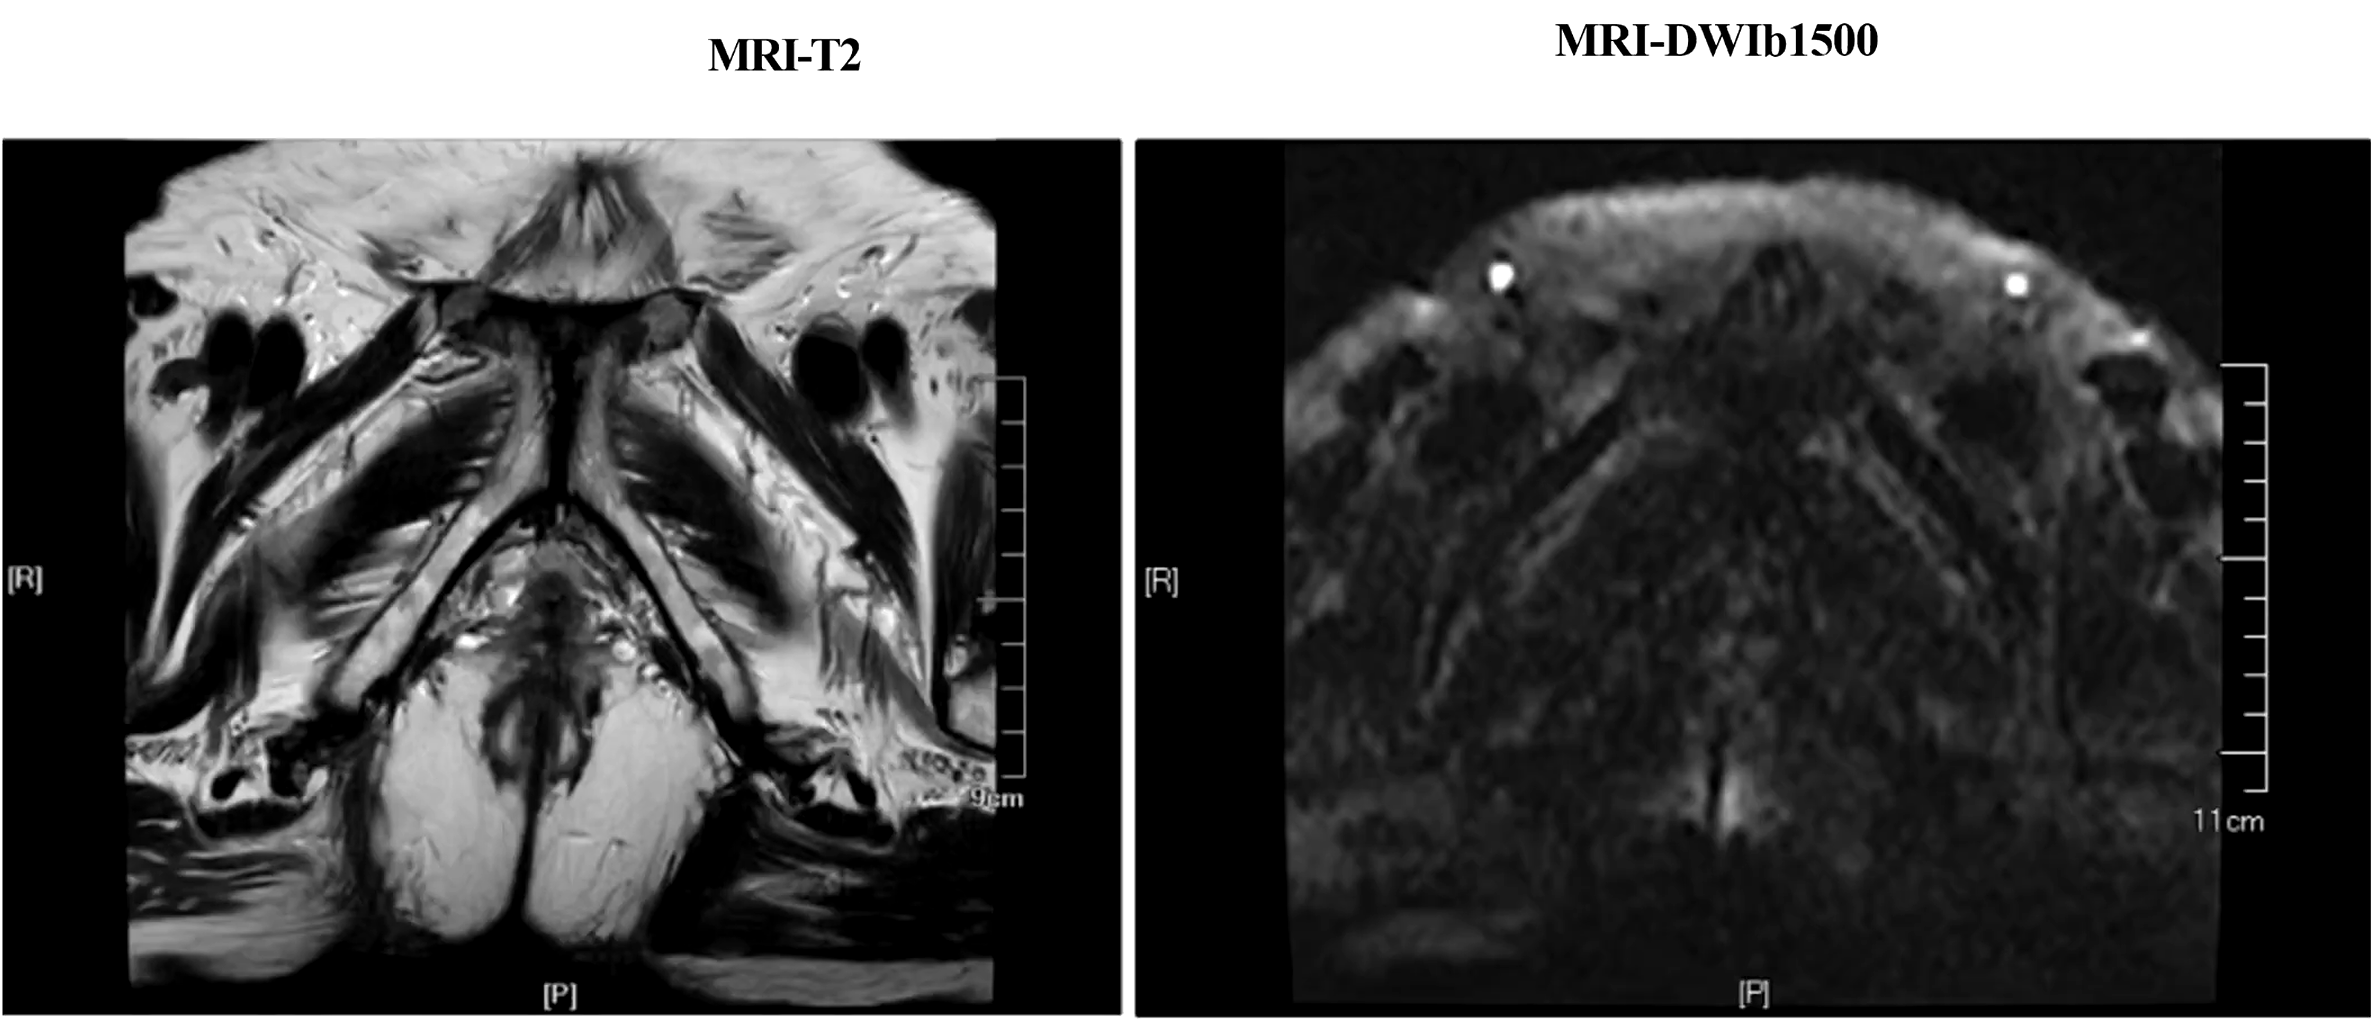

• MRI: 左侧精囊腺受侵,未见明显区域淋巴结及远处转移

图片1.png